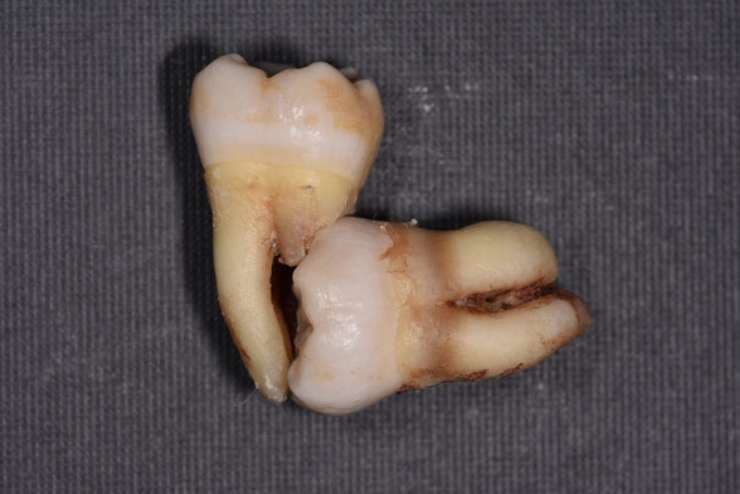

親知らずが原因で手前の歯も抜歯になった症例

上の写真は、親知らずによって、手前の歯の根が溶けてしまっています。

このような状態になると、手前の歯も抜かないといけなくなります。